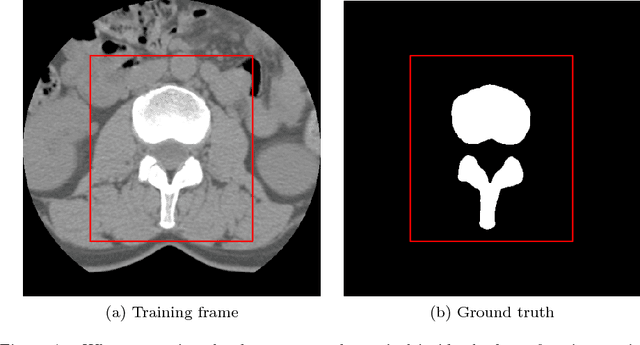

Abstract:There has been a significant increase from 2010 to 2016 in the number of people suffering from spine problems. The automatic image segmentation of the spine obtained from a computed tomography (CT) image is important for diagnosing spine conditions and for performing surgery with computer-assisted surgery systems. The spine has a complex anatomy that consists of 33 vertebrae, 23 intervertebral disks, the spinal cord, and connecting ribs. As a result, the spinal surgeon is faced with the challenge of needing a robust algorithm to segment and create a model of the spine. In this study, we developed an automatic segmentation method to segment the spine, and we compared our segmentation results with reference segmentations obtained by experts. We developed a fully automatic approach for spine segmentation from CT based on a hybrid method. This method combines the convolutional neural network (CNN) and fully convolutional network (FCN), and utilizes class redundancy as a soft constraint to greatly improve the segmentation results. The proposed method was found to significantly enhance the accuracy of the segmentation results and the system processing time. Our comparison was based on 12 measurements: the Dice coefficient (94%), Jaccard index (93%), volumetric similarity (96%), sensitivity (97%), specificity (99%), precision (over segmentation; 8.3 and under segmentation 2.6), accuracy (99%), Matthews correlation coefficient (0.93), mean surface distance (0.16 mm), Hausdorff distance (7.4 mm), and global consistency error (0.02). We experimented with CT images from 32 patients, and the experimental results demonstrated the efficiency of the proposed method.